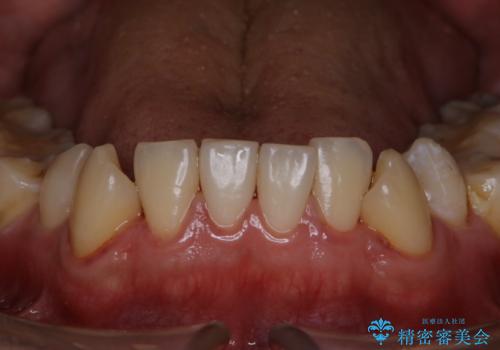

ワイヤー矯正終了時に装置除去と合わせてPMTC

担当医 歯科衛生士